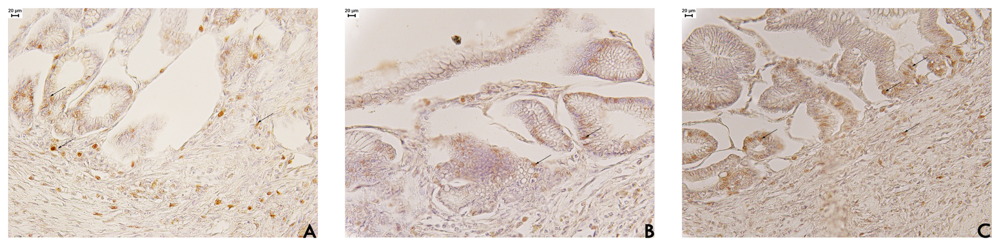

Figure 5. Photomicrographs submucosa from the stomach of rats subjected to different treatments. (A) vehicle (10 mL/kg); (B) cimetidine (100 mg/kg); and (C) ethyl acetate fraction of Alchornea triplinervia (100 mg/kg) immunostained of stomach of rat with COX-2 (scale represents 20 μm). The arrows denote cells COX-2 positive and note the high intensity of COX-2 label at lesion area in C.

To further elucidate the healing process, we measured COX-2 expression during ulcer healing. COX 2 is an important factor for epithelial cell proliferation, migration and re-epithelialisation and reconstruction of gastric glands. Gastric damage is the main side effect associated with inhibition of COX-2 [28]. Despite these clinical findings, there is evidence that COX-2 is protective within the gastrointestinal tract, perhaps explaining why in some studies use of COX-2-selective inhibitors can be associated with ulcer rates higher than placebo. Both COX-1 and COX-2 are expressed in human gastric mucosa, and COX-2-selective inhibitors suppress the formation of prostanoids from healthy samples of human gastric [29].

In animal models of ulceration and gastrointestinal damage, COX-2 products actually promote gastrointestinal healing, and inhibition of COX-2 is required to produce acute gastrointestinal damage [30]. Guo et al. [31] showed that highly selective COX-2 inhibitors delayed ulcer healing impaired angiogenesis in rats. In this study, the expression of COX-2 was increased in gastric tissues obtained from rats in the EAF groups (Figure 5). A marked increase in COX-2 expression was found at the base of the ulcers. This result thus confirmed that COX-2 may play an essential role in the healing of gastric ulcers. Lima et al. [9] observed that EAF was able to increase PGE2 synthesis after acute treatment. Taken together, the action of EAF on COX-2 and PGE2 the gastric mucus barrier, cell proliferation and angiogenesis suggest that it might represent a new strategy of healing gastric ulcers.